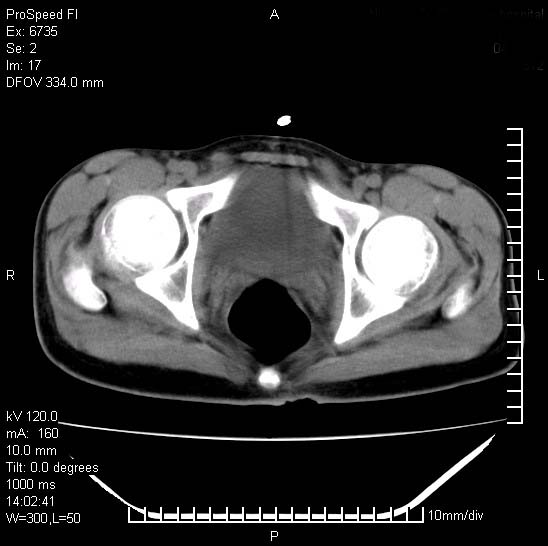

患者自诉胯部疼痛两年余,在当地服用中药,半月前至本院考虑骶髂关节结核,给予抗痨治疗。现发展至右下肢疼痛明显,活动受限,以膝关节处明显,拍膝关节平片无明显异常。

两侧骶骼关节改变,考虑强直性脊炎

左侧骶髂关节面限局性骨破坏,边缘硬化关节腔见钙化物;不出外tb

右侧骶髂关节也有类似改变,只是较左侧轻,首先考虑强直性脊柱炎,不除外结核,建议作hla-b27检查。

典型强脊炎改变,髋关节亦有累及

符合强直性脊柱炎表现。